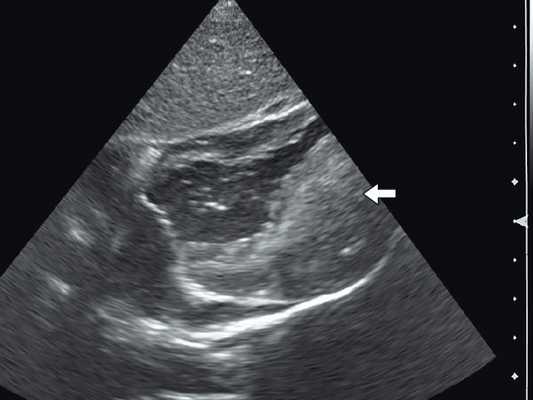

Широкое внедрение в практику ультразвуковой диагностики позволило перейти от аутопсийной статистики к прижизненному выявлению. Эхокардиография - первый метод выявления рабдомиомы сердца и контроля состояния пациента в динамике. Учитывая очень большое число семейных случаев, необходимо обследование всех ближайших родственников, особенно при наличии у них пятен цвета кофе с молоком, депигментированных по типу шагреневой кожи, параунгвальных и параореолярных фибром, ранних миом матки, инфантильных спазмов, судорожных припадков и других признаков факоматозов. При семейных обследованиях рабдомиомы сердца могут выявляться у совершенно бессимптомных носителей (рис. 1, 2).

Рис. 1. Эхокардиограмма ребенка (девочки) с рабдомиомой. Крупный узел рабдомиомы в межжелудочковой перегородке (1) и менее крупные узлы в задней стенке левого желудочка (2). Эхоплотность образований выше, чем миокарда.

Рис. 2. Эхокардиограмма матери этого же ребенка. В межжелудочковой перегородке несколько эхоплотных образований (стрелки).

Рабдомиома сердца эхографически выглядят как достаточно четко очерченные образования. Чаще всего располагаются в миокарде левого желудочка, реже - в правом, еще реже - в предсердиях, кавоатриальных и атриовентрикулярных соединениях, эпикарде. Метастазирование не типично [8]. Наличие двух и более рабдомиом четко коррелирует с туберозным склерозом, одиночные рабдомиомы сердца такой связи, как правило, не имеют. По нашему опыту (18 пациентов), чем меньше объем новообразования, тем выше акустическая плотность, приближающаяся к эталонной эхоплотности (эндо-, эпи- и перикард). Эхоплотность больших рабдомиом практически не отличается от эхоплотности миокарда. В толще новообразования выявляются мелкие эхонегативные очажки (области некрозов) и эхопозитивные очажки (отложения кальция) (рис. 3).

Рис. 3. Эхокардиограмма гигантской рабдомиомы (стрелка) у девочки марфаноидного статуса без признаков туберозного склероза (субксифоидальный доступ).